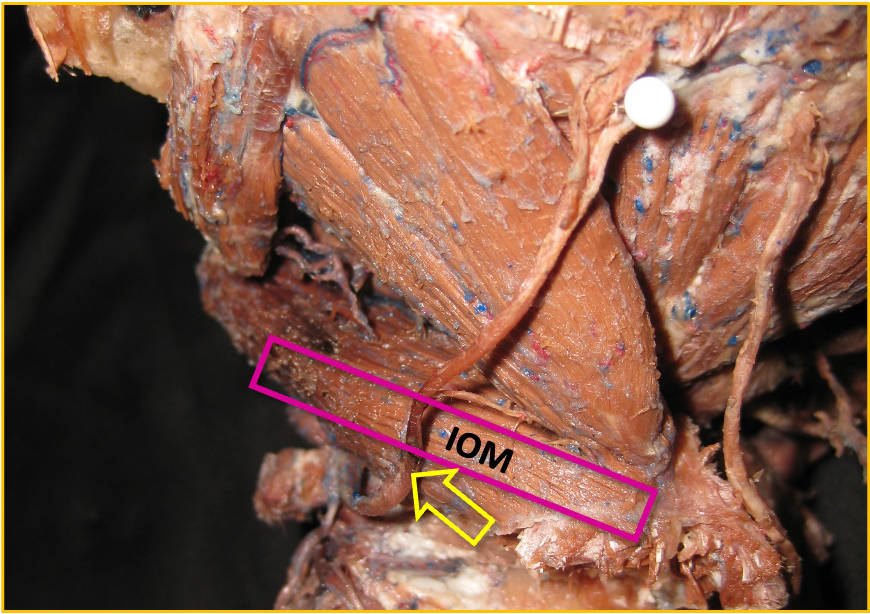

US-Darstellung und experimentelle Blockade (Pfeilköpfe: Nadel) des N. cutaneus femoris lateralis an einer Körperspenderin. Mittlerweile gängige Anwendung in der Regionalanästhesie und Schmerztherapie

Der hell erscheinende N. cutaneus femoris lateralis (Pfeil) wird am Oberschenkel in seinem „fettgefüllten Flachtunnel“ (im US dunkel!) am leichtesten aufgefunden: “POV“ (Point of Optimal Visibility) nach Prof. Moriggl.